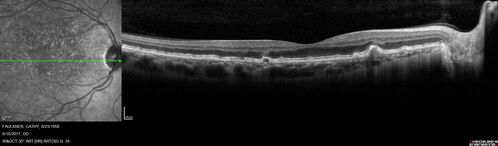

Soft Drusen

63 year old female with 20/16 vision both eyes